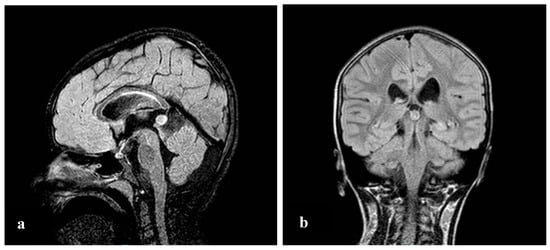

| Our patient | 46, XX, der(8)del(8)(p23.1)invdup(p12p23.1) | + | Developmental and speech delay. No meaningful sentences. Hypotonia. Hypothyroidism. Prominent forehead, arched eyebrow, thin nose with rounded tip and anteverse nostrils, flat filter, thin down-turned lips, slight micrognathia, low-set posteriorly rotated ears. Single palmar crease on the right hand and bilateral IV-V fingers clinodactyly. Hypertrichosis, previous sacrococcygeal fistula sign. Extra-rotation of the lower limbs, varus position of both the knees, flat feet. Bilateral cutaneous dimples on both elbows and knees, shield chest, inverted nipples, winged shoulder blades. Emotiveness, impulsiveness, decreased attention span. Dilatation of lateral ventricles, pineal gland’s small ectasia, moderate cystic cisterna magna’s ectasia, retrocerebellar cystic ectasia. Global chorio-retinic dystrophia, pale papilla with clear boundaries, peri-papillar pigmentary ring. Sialorrhea and extravelic palatin tonsils, ogival palate, type C tympanogram with absent stapedial reflex on the left. |